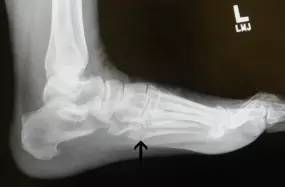

14.第五跖骨骨折

第五跖骨基底部骨折的不同类型:Stress 骨折;Jones 骨折:第五跖骨基底部以远 1 英寸内的骨折称为 Jones 骨折;Avulsion 骨折。

(来源:Radiopaedia)

Stress 骨折(来源:OrthoInfo-AAOS)

Jones 骨折正位片(来源:Radiopaedia)

Jones 骨折斜位片(来源:Radiopaedia)

第五跖骨骨折还有 dancer’s fracture。

dancer’s fracture 正位片(来源:footEducation)

dancer’s fracture 侧位片(来源:footEducation)